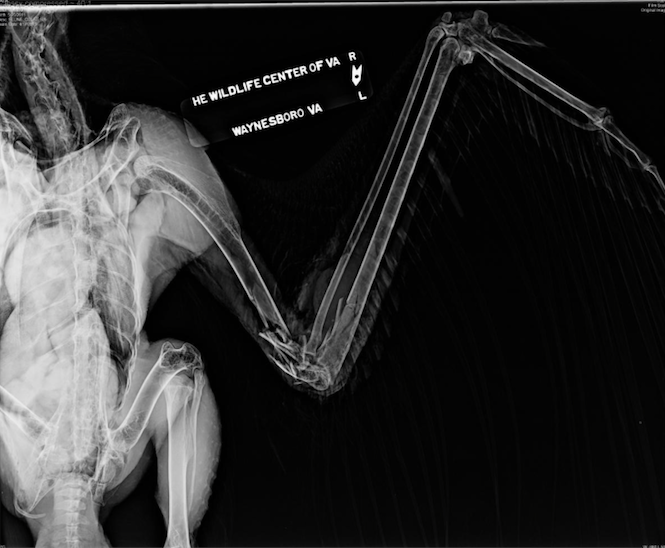

The injured bird was taken the center the same day. That’s when Dr. Meghan Feeney found that a large laceration on the left wing. Muscle and bone was exposed and he bird was bleeding. Radiographs showed the wing bone fractured into multiple fragments, a fracture of the left ulna and a collapsed elbow joint.

The veterinarians also spotted two pellets on the X-rays. One was above the tail, and the other, near the right ulna.

“There were also changes to the right ulna, indicated that the eagle sustained previous trauma that had healed. It’s likely that the bird’s ulna was fractured from a gunshot wound,” the center said.